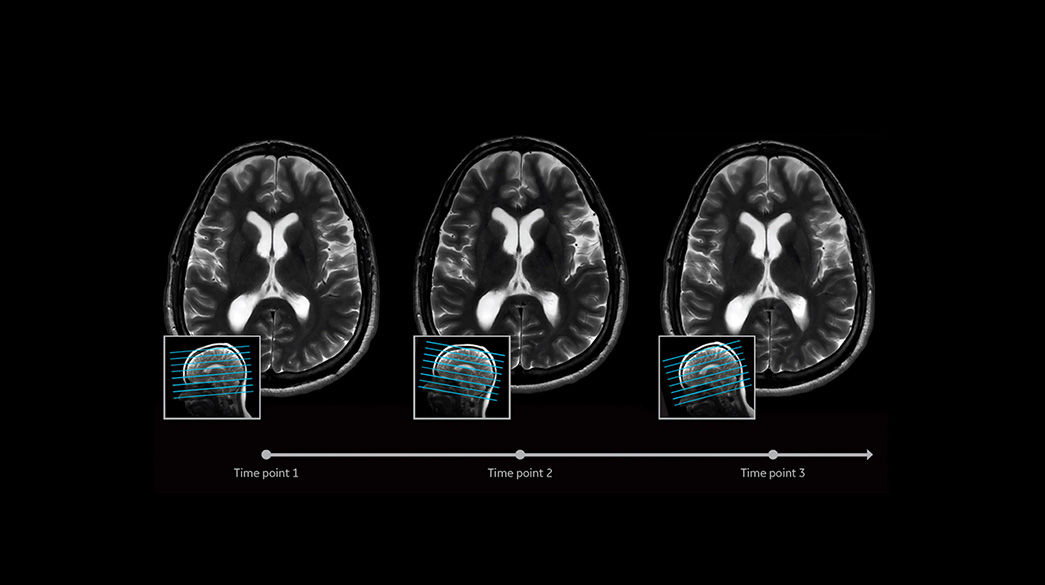

Consistent

Motion and distortion-reduced scans with high-resolution and contrast

Diagnostic confidence and consistency

AIR-Recon-DL1040-x-585

Learn more

Sonic-DL1040-x-585